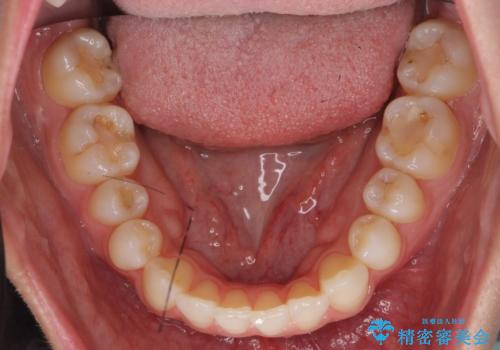

- 前歯のがたつきと小さな歯の形を治したいと来院。

前から2番目の歯が小さく、細くとがった形になっていました。

大きくしようにも、幅が少ない上に、また、内側に入ってしまっているため、矯正治療で前歯を並べてからセラミックでかぶせることにしました。

いきなりセラミックでかぶせるよりも手間をかけた分、自然な仕上がりになっています。

先に矯正治療をすることで、下の前歯を内側に入れることができ、上の歯のセラミックの幅や厚みを取ることができました。